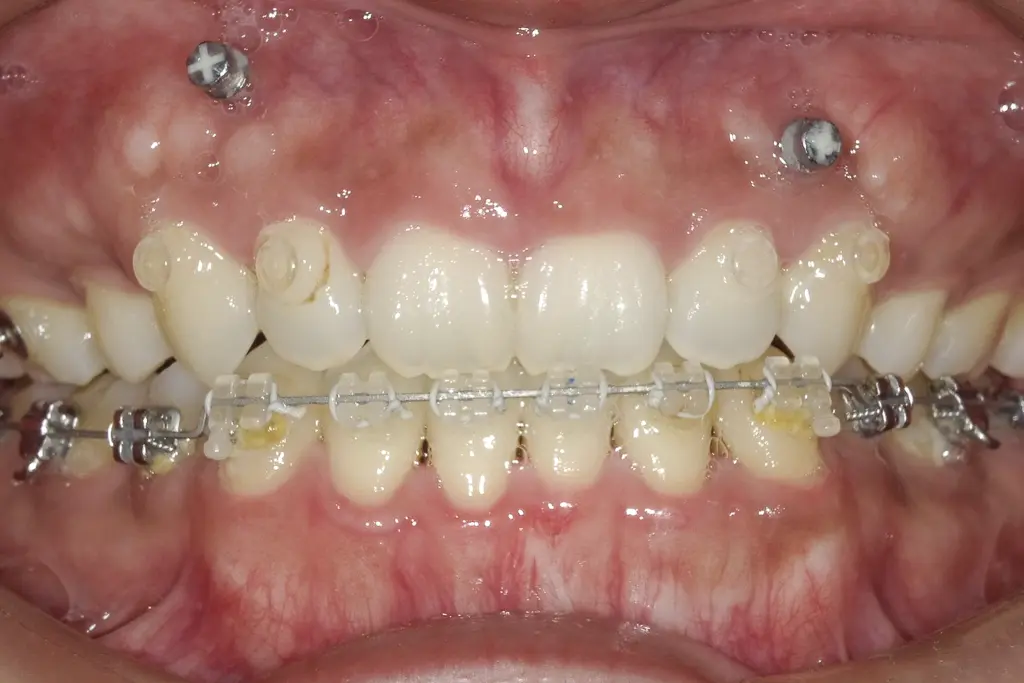

アンカースクリューにて歯の位置を調整しています

歯の位置をアンカースクリューにて調整しています。

口元や舌のトレーニングをします

飲み込む時に舌が前に出てしまう癖が見られたのでトレーニングで正しい使い方をお伝えします。歯並びが整ってくると口元の筋肉も使いやすくなってきます。

治療内容:第1小臼歯を4本抜歯し、ワイヤータイプの装置で矯正しました。